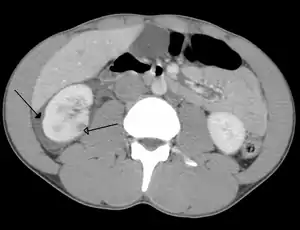

| Abdominal trauma resulting in a right kidney contusion (open arrow) and blood surrounding the kidney (closed arrow) as seen on CT | |

The kidneys may also be injured; they are somewhat but not completely protected by the ribs.[6] Kidney lacerations and contusions may also occur.[13] Kidney injury, a common finding in children with blunt abdominal trauma, may be associated with bloody urine.[13] Kidney lacerations may be associated with urinoma or leakage of urine into the abdomen.[4] A shattered kidney is one with multiple lacerations and an associated fragmentation of the kidney tissue.[4]